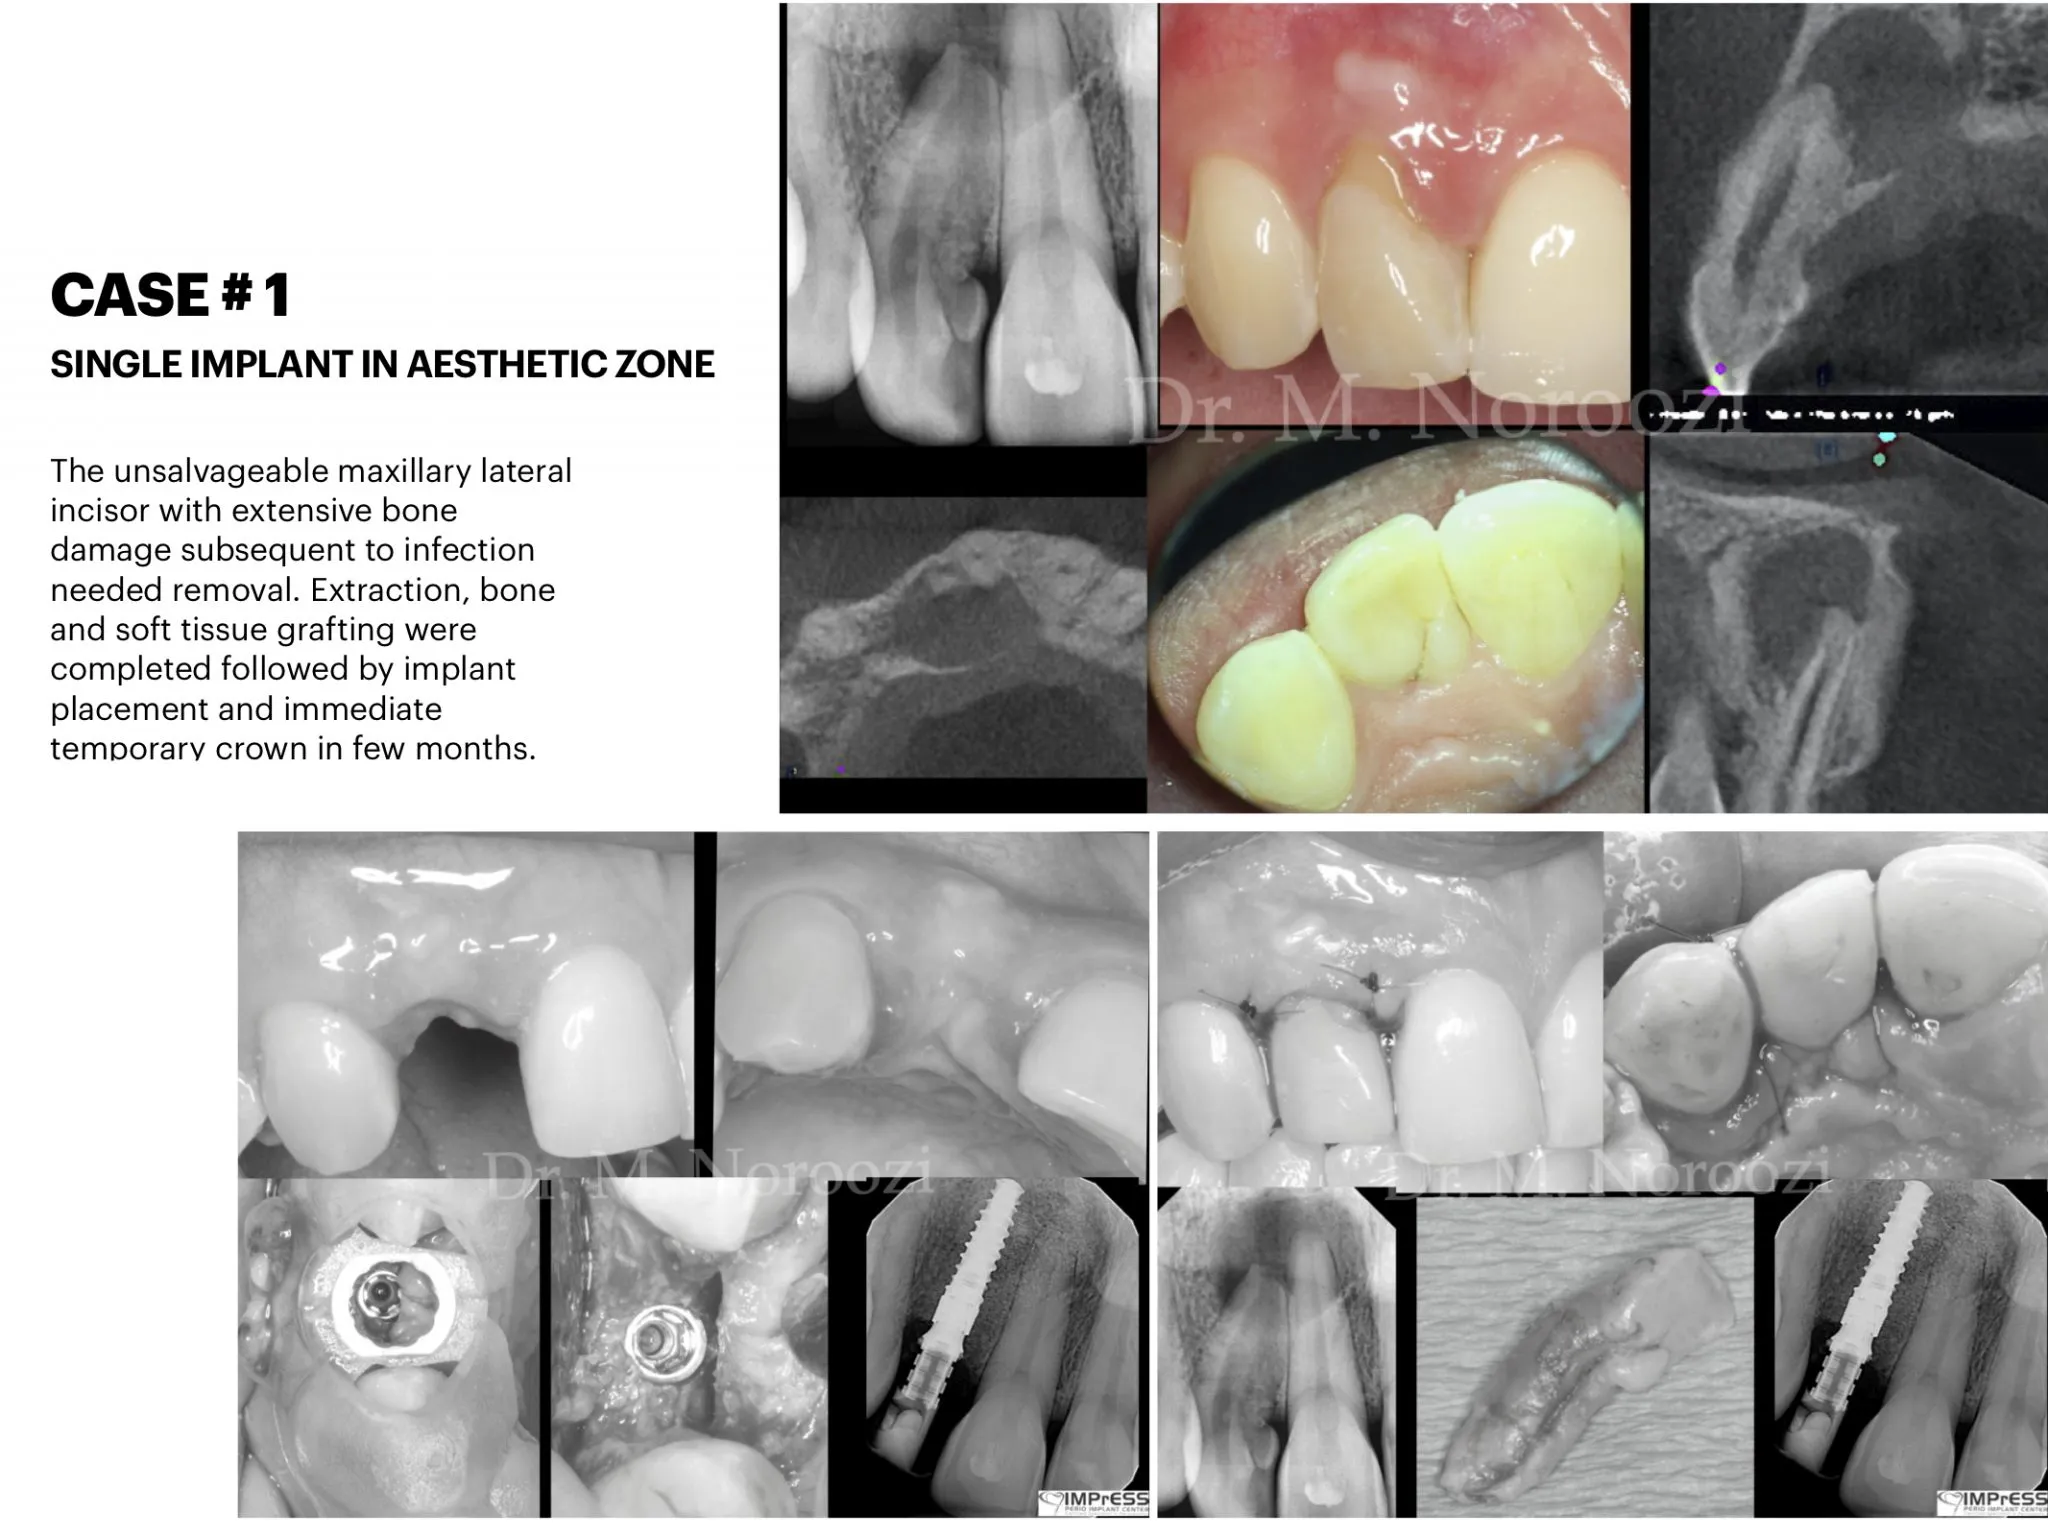

Before & Afters of Dental Implant Patients

Complete Dental Implant Cases Gallery

General Disclaimer: The results in the photographs are examples only and do not imply any certainty of the result of a procedure, and all outcomes are subject to the circumstances of the individual patient.